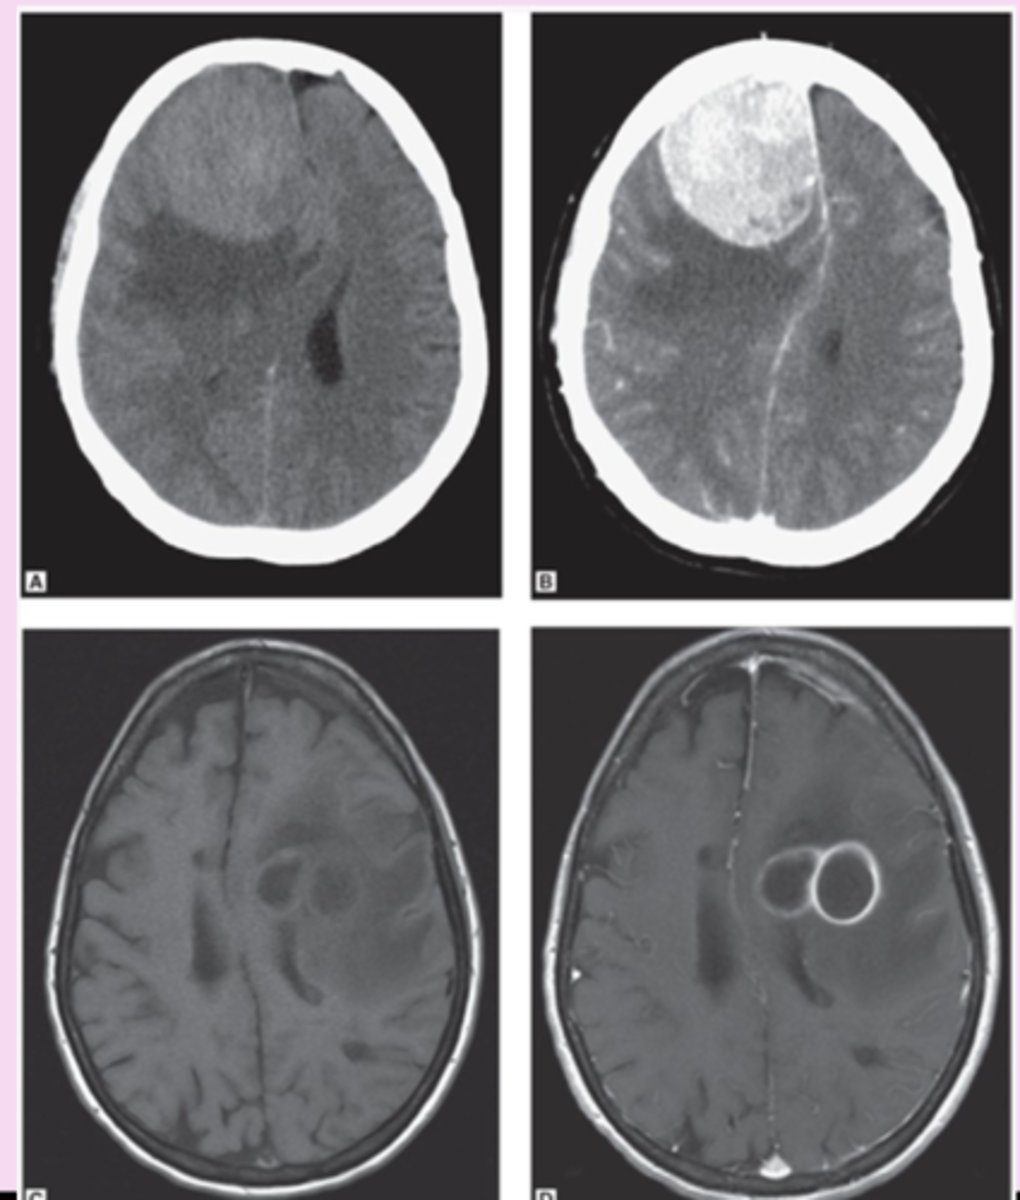

CT interpretation

denser tissue is brighter (hyperdense)

less dense is darker (hypodense)

bone is white, air is black

brain window- structures to be identified and differentiated

bone window- best for visualizing bone

white matter appears

blacker than grey matter because it has high content of myelinated axons and lower density

cytotoxic edema

loss of grey-white differentiation

-cant distinguish them from each other

vasogenic edema

accentuation of grey-white differentiation

-tumor or abscess